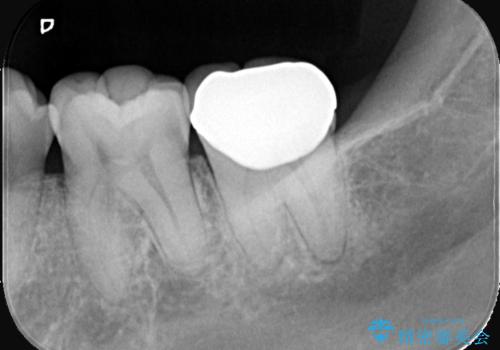

二か月程期間を開け症状が出ていないことと、歯髄診断を再度行い正常反応を確認した後、セラミッククラウン補綴修復を行いました。